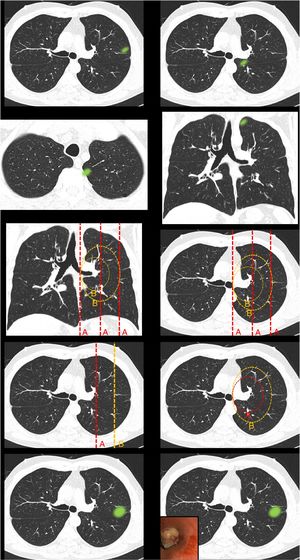

Definición de centralidad (fig. 1): en este bloque se valoró la uniformidad de criterio para definir centralidad.

Figura 1.En este bloque se valoró la uniformidad de criterio para definir centralidad. Imagen 1: ¿Considera que el nódulo tiene localización? Central/Periférica. Imagen 2: ¿Considera que el nódulo tiene localización? Central/Periférica. Imágenes 3a y 3b ¿Considera que el nódulo tiene localización? Central/Periférica. Imagen 4: ¿Cuál de las siguientes líneas define mejor centralidad? Líneas A/Líneas B. Imagen 5: ¿Cuál de las siguientes líneas define mejor centralidad? Líneas A/Líneas B. Imagen 6: ¿Cuál de las dos líneas delimita un tumor central? Línea A (1/3 central)/Línea B (2/3 centrales). Imagen 7: ¿Cuál de las dos líneas delimita un tumor central? Línea A (1/3 central)/Línea B (2/3 centrales). Imagen 8: ¿Considera que el nódulo tiene localización? Central/Periférica. Imagen 9: ¿Considera que el nódulo tiene localización? Central/Periférica.

Definición de centralidadCasi la mitad de los participantes escogieron «lesiones en contacto con las estructuras hiliares» (49,7%) como definición de localización tumoral central (tabla 1 [pregunta 1]). Las líneas más elegidas para delimitar centralidad fueron líneas B (líneas concéntricas al hilio pulmonar) (89%) (imágenes 4 y 5). La imagen «control positivo lesión periférica» (imagen 1) fue catalogada como periférica por la totalidad de los participantes mientras que la imagen «control positivo lesión central» (imagen 2) fue catalogada como central por tres cuartas partes de los participantes. La imagen escogida como «control positivo lesión central SEPAR» (imágenes 3a y 3b) fue mayormente catalogada como periférica (71,1%). La mayoría de los participantes votaron por delimitar la centralidad en el 1/3 interno del hemitórax, en lugar de los 2/3 internos tanto para las líneas A (imagen 6) (310 [72,3%]) como para las líneas B (imagen 7) (339 [79%]). La presencia de lesión endobronquial influyó en la consideración de una lesión como central ya que la misma imagen pasó de ser catalogada central por solo un 7% de los participantes (imagen 8) a un 36,1% (imagen 9) al añadir la información de una imagen endobronquial (test exacto de Fisher p< 0,01). Al contrario de otras preguntas, en esta imagen sí se observaron diferencias estadísticamente significativas entre especialidades (test exacto de Fisher p< 0,01) (tabla 1).